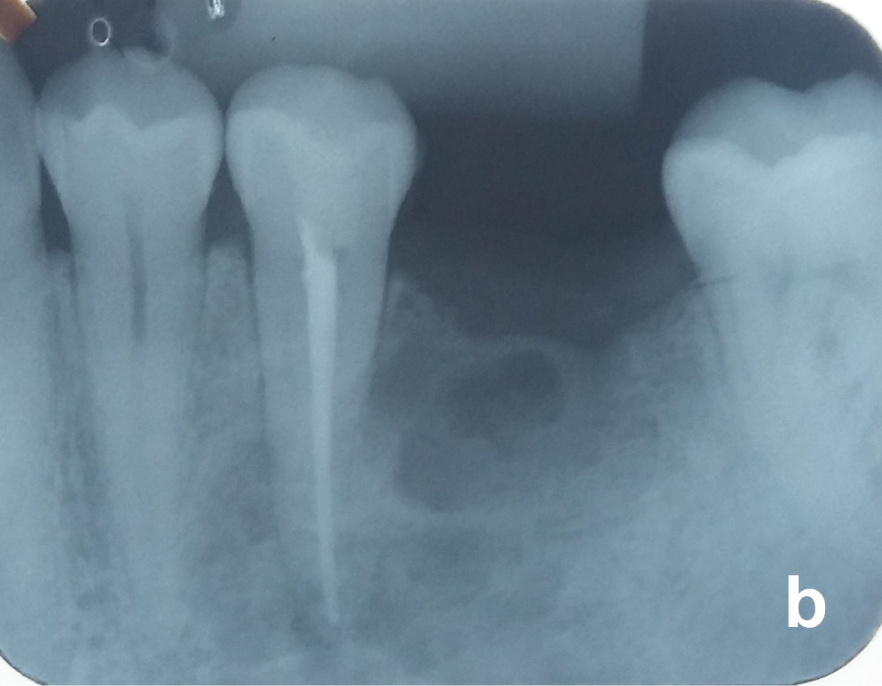

Nonvital teeth close to the OKC may be endodontically treated and maintained (Figure 5a and Figure 5b) but those with the cyst adhered on the radicular surface or with radicular resorption by the OKC should be removed. After total removal of the OKC, patients should receive a yearly radiological follow-up the first five years and beyond that every two years. Recurrences may occur over as long a period of 25 years [18].

Figure 5A: Same case of the figure 2. Unilocular OKC with a well-defined border between the nonvital tooth 35 and the vital tooth 37. Observe that the periodontal ligament of both teeth are preserved. View Figure 5A

Figure 5B: Tooth 35 was endodontically treated before the surgery. View Figure 5B